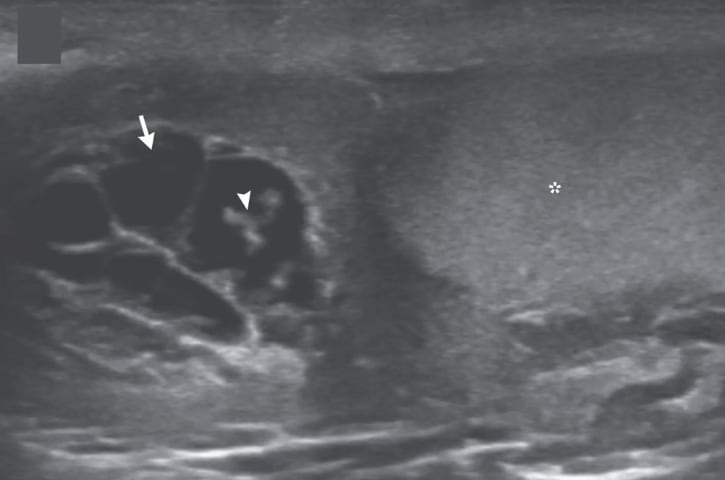

En ellas se aprecia a los gusanos en movimiento dentro de un canal linfático dilatado del testículo; tubos delgados que transportan líquido y glóbulos blancos en el escroto.

Durante el examen, los profesionales detectaron sensibilidad e hinchazón en el lado derecho del escroto, y una ecografía posterior mostró a los gusanos bailando en el interior de su testículo.

Asimismo, con las ondulaciones de gusanos vivos que han migrado a los canales linfáticos, se experimenta dilatación y disfunción en el testículo.